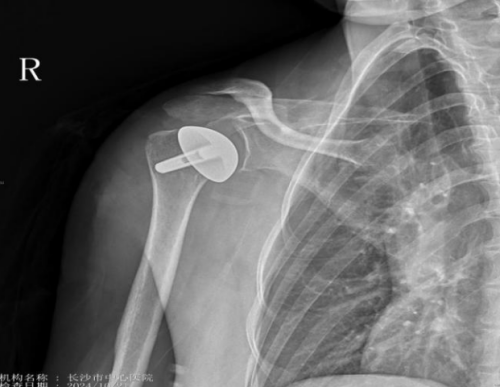

术后影像